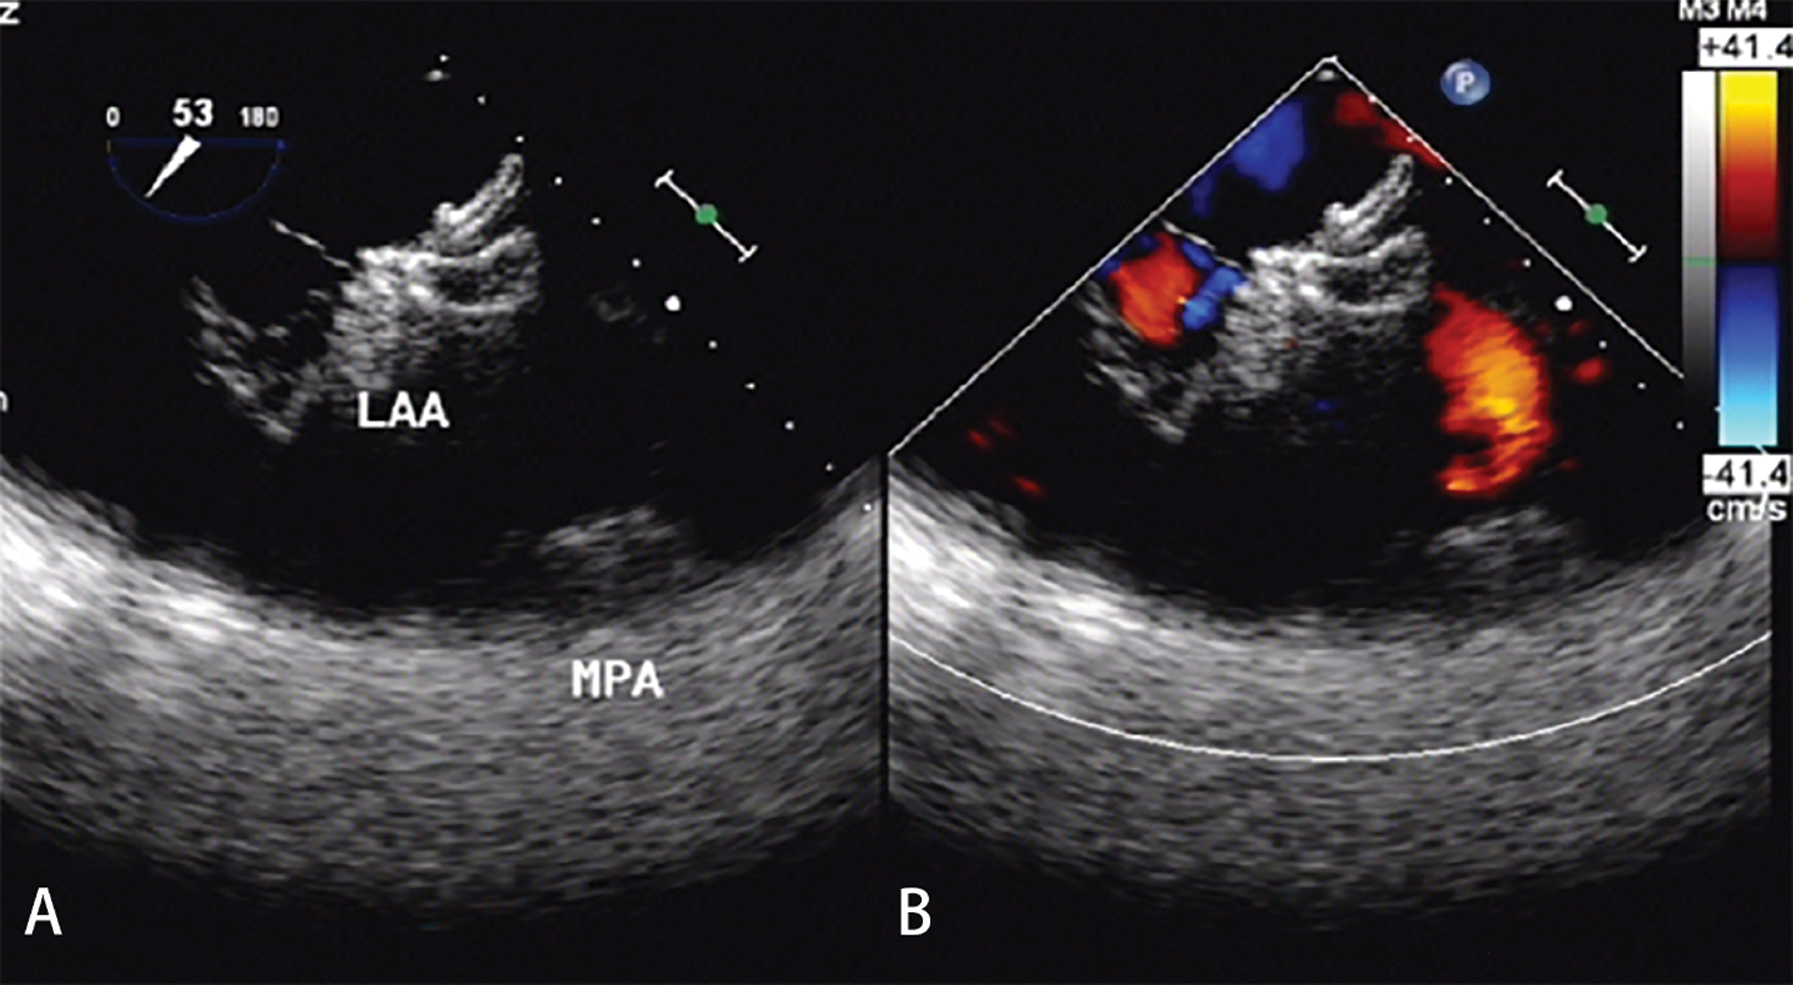

Clinical follow-up was completed at a median follow-up time of 37.6 months. No device-related deaths were observed during the whole follow-up period. No new-onset mitral valve regurgitation more severe than moderate degree was noted. One patient complained of palpitation 34 days after the procedure at a clinic visit and recovered from symptomatic treatment. Neither cerebrovascular/peripheral vascular embolic events nor hemorrhage occurred during a mean follow-up of 38.4 ± 3.9 months. Twenty-six patients (96.3%) completed 30 days and 90 days of follow-up by TTE and 180 days of follow-up by TEE. The results demonstrated the proper positioning of both devices in all patients. There was no thrombosis or residual leakage into the LAA occluders (Fig. 3). There were no significant changes in ejection fraction score after closure (F = 0.82, P = 0.52). Of the 21 patients with NYHA Class III, 19 had significant improvements to NYHA Classes I or II. One ASD patient was re-hospitalized for deterioration of heart failure 140 days after closure. The other high mean pulmonary artery pressure patient with hole ASD occluder had no significant improvement in cardiac function at follow-up every year. No infective endocarditis was observed during the follow-up period. 81.5% of patients were free from major or minor adverse events during mid-and long-term follow-up.

Figure 3: TEE examination after 180 days of follow-up. (A) There was no thrombosis with good shape and a fixed position of the LAA occluder. (B) There was no residual leakage into the LAA occluder